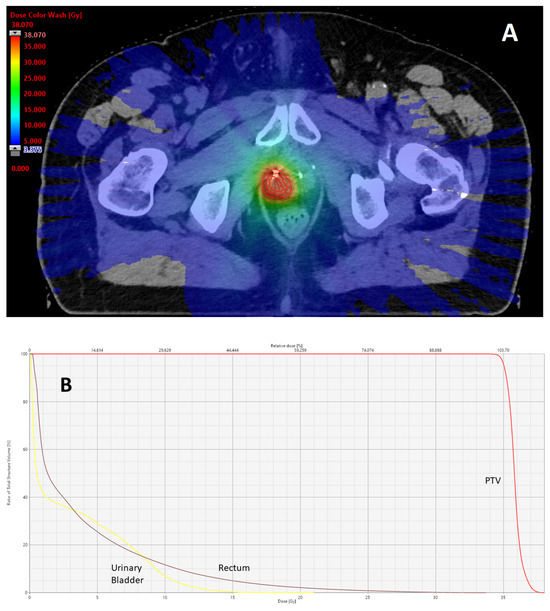

Prostate–Rectum Spacing from Apex to Base and Its Impact on Organs-At-Risk Dosimetry in Prostate Cancer SBRT

by Victor C. Ng, Jill Steele and Edward Soffen

Radiation 2026, 6(1), 8; https://doi.org/10.3390/radiation6010008 - 24 Feb 2026

Viewed by 344

Abstract

Stereotactic body radiation therapy (SBRT) for localized prostate cancer delivers high doses per fraction, making dose constraints for the rectum and other organs at risk critical during treatment planning. This study evaluated the association between prostate–rectum separation, achieved with a biodegradable balloon rectal [...] Read more.

Stereotactic body radiation therapy (SBRT) for localized prostate cancer delivers high doses per fraction, making dose constraints for the rectum and other organs at risk critical during treatment planning. This study evaluated the association between prostate–rectum separation, achieved with a biodegradable balloon rectal spacer at different anatomical levels, and corresponding organ-at-risk dose patterns. Thirty-three patients underwent transperineal balloon spacer implantation followed by SBRT to 36.25 Gy in five fractions. Prostate–rectum separation at the apex, mid-gland, and base were measured on CT and/or MRI and categorized as <10 mm, 10–14 mm, or ≥14 mm. Rectal dose–volume parameters and mean doses to the rectum, bladder, and penile bulb were assessed using linear regression analyses and group comparisons at 14 mm separation. Mean prostate–rectum separation was 16.6 mm overall, with minimal high-dose rectal exposure observed. Increasing separation was associated with reduced rectal dose–volume parameters at the apex and mid-gland, while greater base separation corresponded primarily to lower bladder mean dose. Increased apical separation was also associated with reduced penile bulb mean dose. No acute gastrointestinal toxicity was observed, and genitourinary toxicity was limited to low-grade events. These findings indicate that prostate–rectum separation varies by anatomical level and is associated with distinct organ-at-risk dose relationships in prostate SBRT. Full article